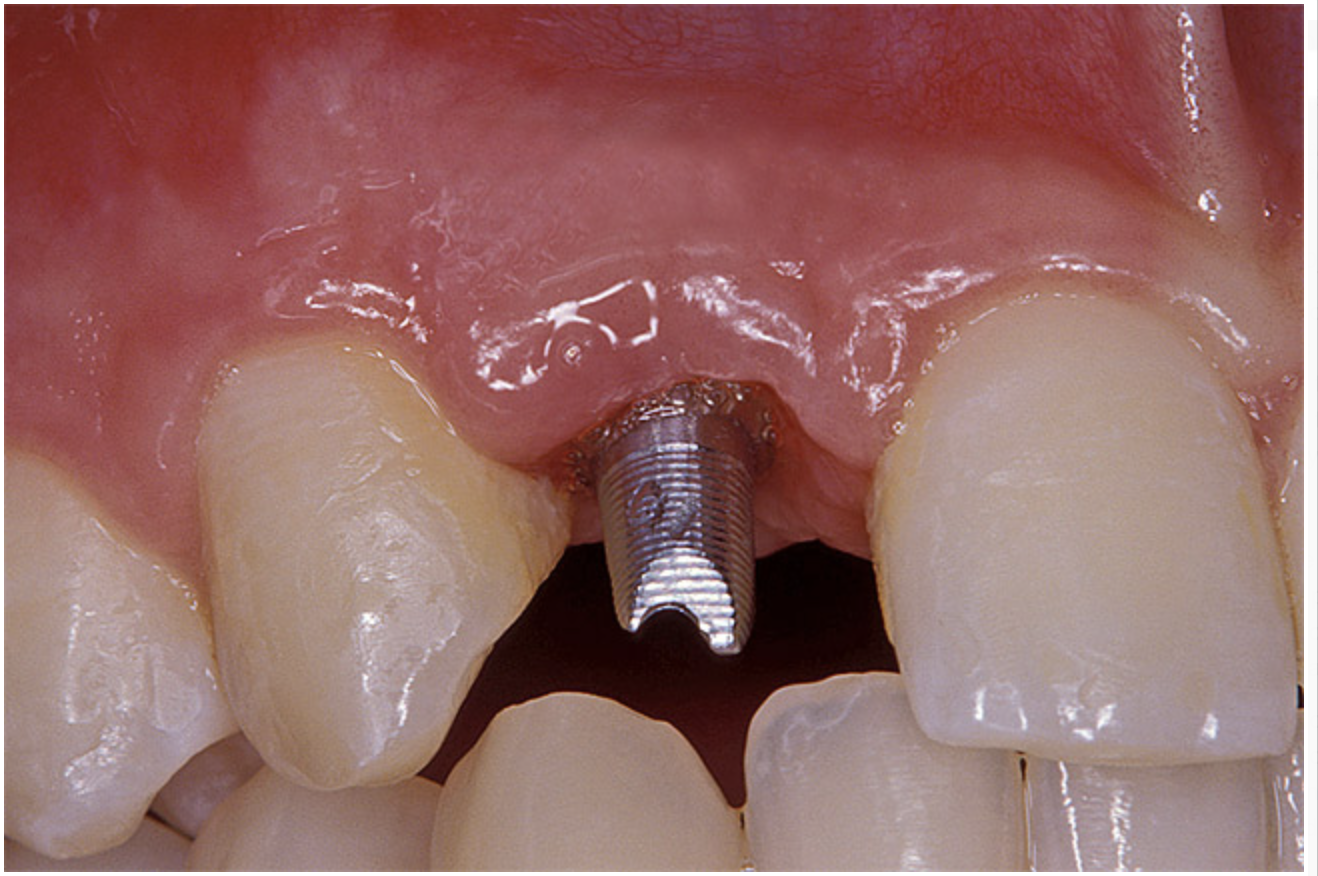

Before the day of surgery, the patient was seen by the orthodontist for the removal of the orthodontic brackets. The patient still was not pleased with the position of the two centrals, and it was determined that this would be addressed after implant placement (Figure 13A). The anatomical variations of the crestal tissue and lack of interdental papilla can be appreciated in the close-up views of the right and left sites (Figure 13B and 13C). There were no surprises on the day of surgery as all of the decisions were made during the planning phase, before the scalpel ever touched the patient. The occlusal view of the CT 3D model revealed the wider alveolar ridge on the right side and thinner crest on the left side (Figure 14A). This was confirmed when the full thickness mucoperiosteal flaps were elevated, and the underyling bone revealed (Figure 14B). The tooth-borne templates were designed to facilitate the drills and drilling sequence specific to the diameters of the predetermined implants (Figure 15A). Each template contained an embedded 5-mm long stainless steel tube, which was approximately 0.2-mm wider than each drill (just wide enough to allow for the drills to rotate freely). Once positioned over the natural teeth, the template was secure and offered precision accuracy in transferring the implant locations from the original software-designed plan, allowing the potential for internal and external irrigation (Figure 15B).

Figure 13a  Before implant surgery, the orthodontic brackets were removed, revealing (A) the position of the centrals, and (B, C) the anatomical variations of the crestal tissue and lack of interdental papilla.

Figure 13a

Figure 13b  Before implant surgery, the orthodontic brackets were removed, revealing (A) the position of the centrals, and (B, C) the anatomical variations of the crestal tissue and lack of interdental papilla.

Figure 13b

Figure 13c  Before implant surgery, the orthodontic brackets were removed, revealing (A) the position of the centrals, and (B, C) the anatomical variations of the crestal tissue and lack of interdental papilla.

Figure 13c